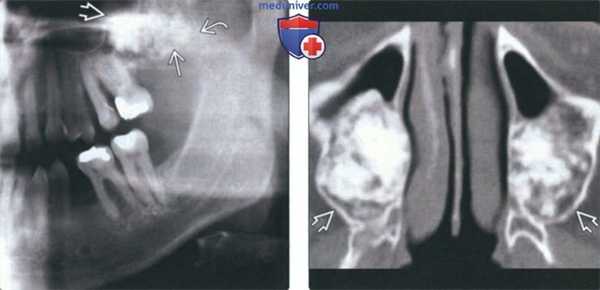

(Слева) На панорамной рентгенограмме в задних отделах нижней челюсти справа определяется большое просветление с фестончатыми краями, отграниченное кортикальной пластинкой, приводящее к вздутию нижнего края нижней челюсти и альвеолярного гребня в области третьего моляра. Аналогичное просветление меньшего размера определяется у вершин корней премоляров. Эти поражения представляют собой проаые коаные киаы, сформировавшиеся в областях ЦКД.

(Справа) На корональной КТ в костном окне с обеих сторон нижней челюсти у этого же пациента определяются экспансивные простые костные кисты.